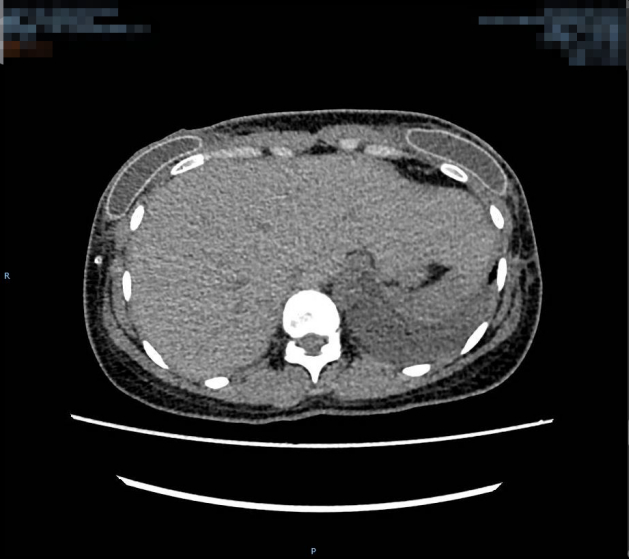

该患者胸部增强CT术前(左图)术后(右图)对比图,其中术前大小约:267mm×100mm×293mm(左),125mm×270mm×340mm(右)

医生初步诊断王女士为双侧多发实性结节、乳房肥大症(巨乳症),乳房体积明显增大,下垂严重,乳腺腺体结构紊乱伴增生。乳房组织受内分泌系统影响非常大,孕期随着雌性荷尔蒙的分泌,乳房随之增长其实是很常见的情况。但像王女士如此明显的变化确实十分少见。

医生给王女士进行了手术,全程历时近9小时,术中切除多余的乳腺组织共26斤,同时顺利进行乳头乳晕复合组织瓣移植,重塑双侧乳房。